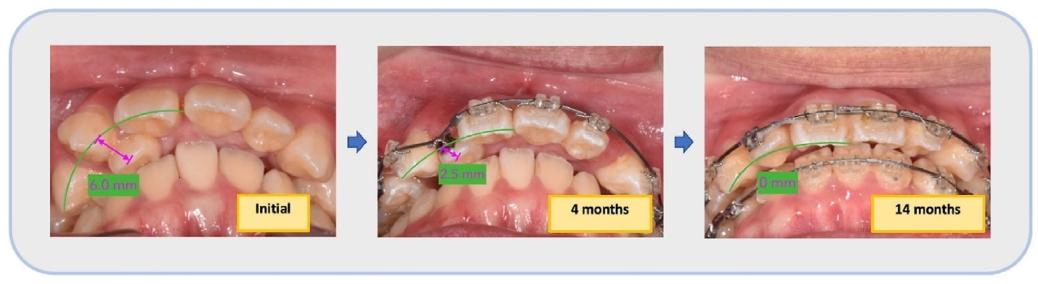

3. 阻生牙牵引与间隙利用(4-14个月)

✅ 开圈弹簧拉开#11与#13间隙,为#12“腾出位置”

✅ 轻力牵引+ISW弹性引导,逐步将阻生的#12纳入牙弓

第三月可见开圈弹簧为阻生牙创造间隙